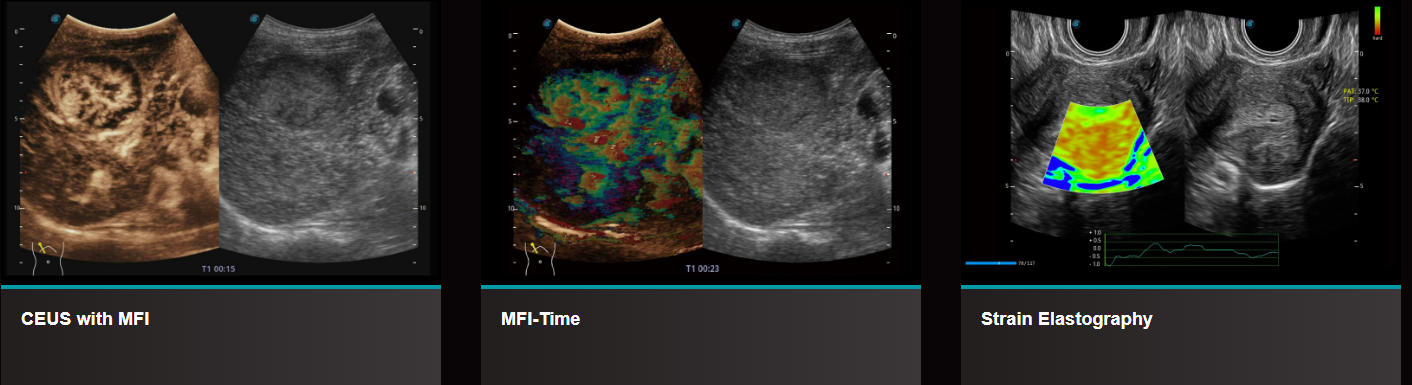

MFI-Thời Gian: MFI Time cung cấp chế độ xem tham số được mã hóa bằng màu, cho biết thời gian hấp thu của các chất tương phản trong các giai đoạn tưới máu khác nhau để phân biệt các mô tốt hơn. Nó giúp quan sát hiệu quả sự phân bổ lưu lượng máu của khối u.

CEUS với MFI: Hiển thị tưới máu nâng cao theo dõi các quần thể bong bóng nhỏ, ngay cả ở các vùng ngoại vi và được tưới máu thấp.

Strain Elastography: Đo độ đàn hồi của mô theo thời gian thực được hiển thị dưới dạng bản đồ màu để phát hiện các bất thường tiềm ẩn trong mô bình thường. Có sẵn trên các đầu dò tuyến tính Liearn, Convex và âm đạo để bao quát nhiều vùng phân tích bán định lượng dựa trên tỷ lệ biến dạng giữa tổn thương và mô bình thường có thể cho thấy độ cứng tương đối của tổn thương.